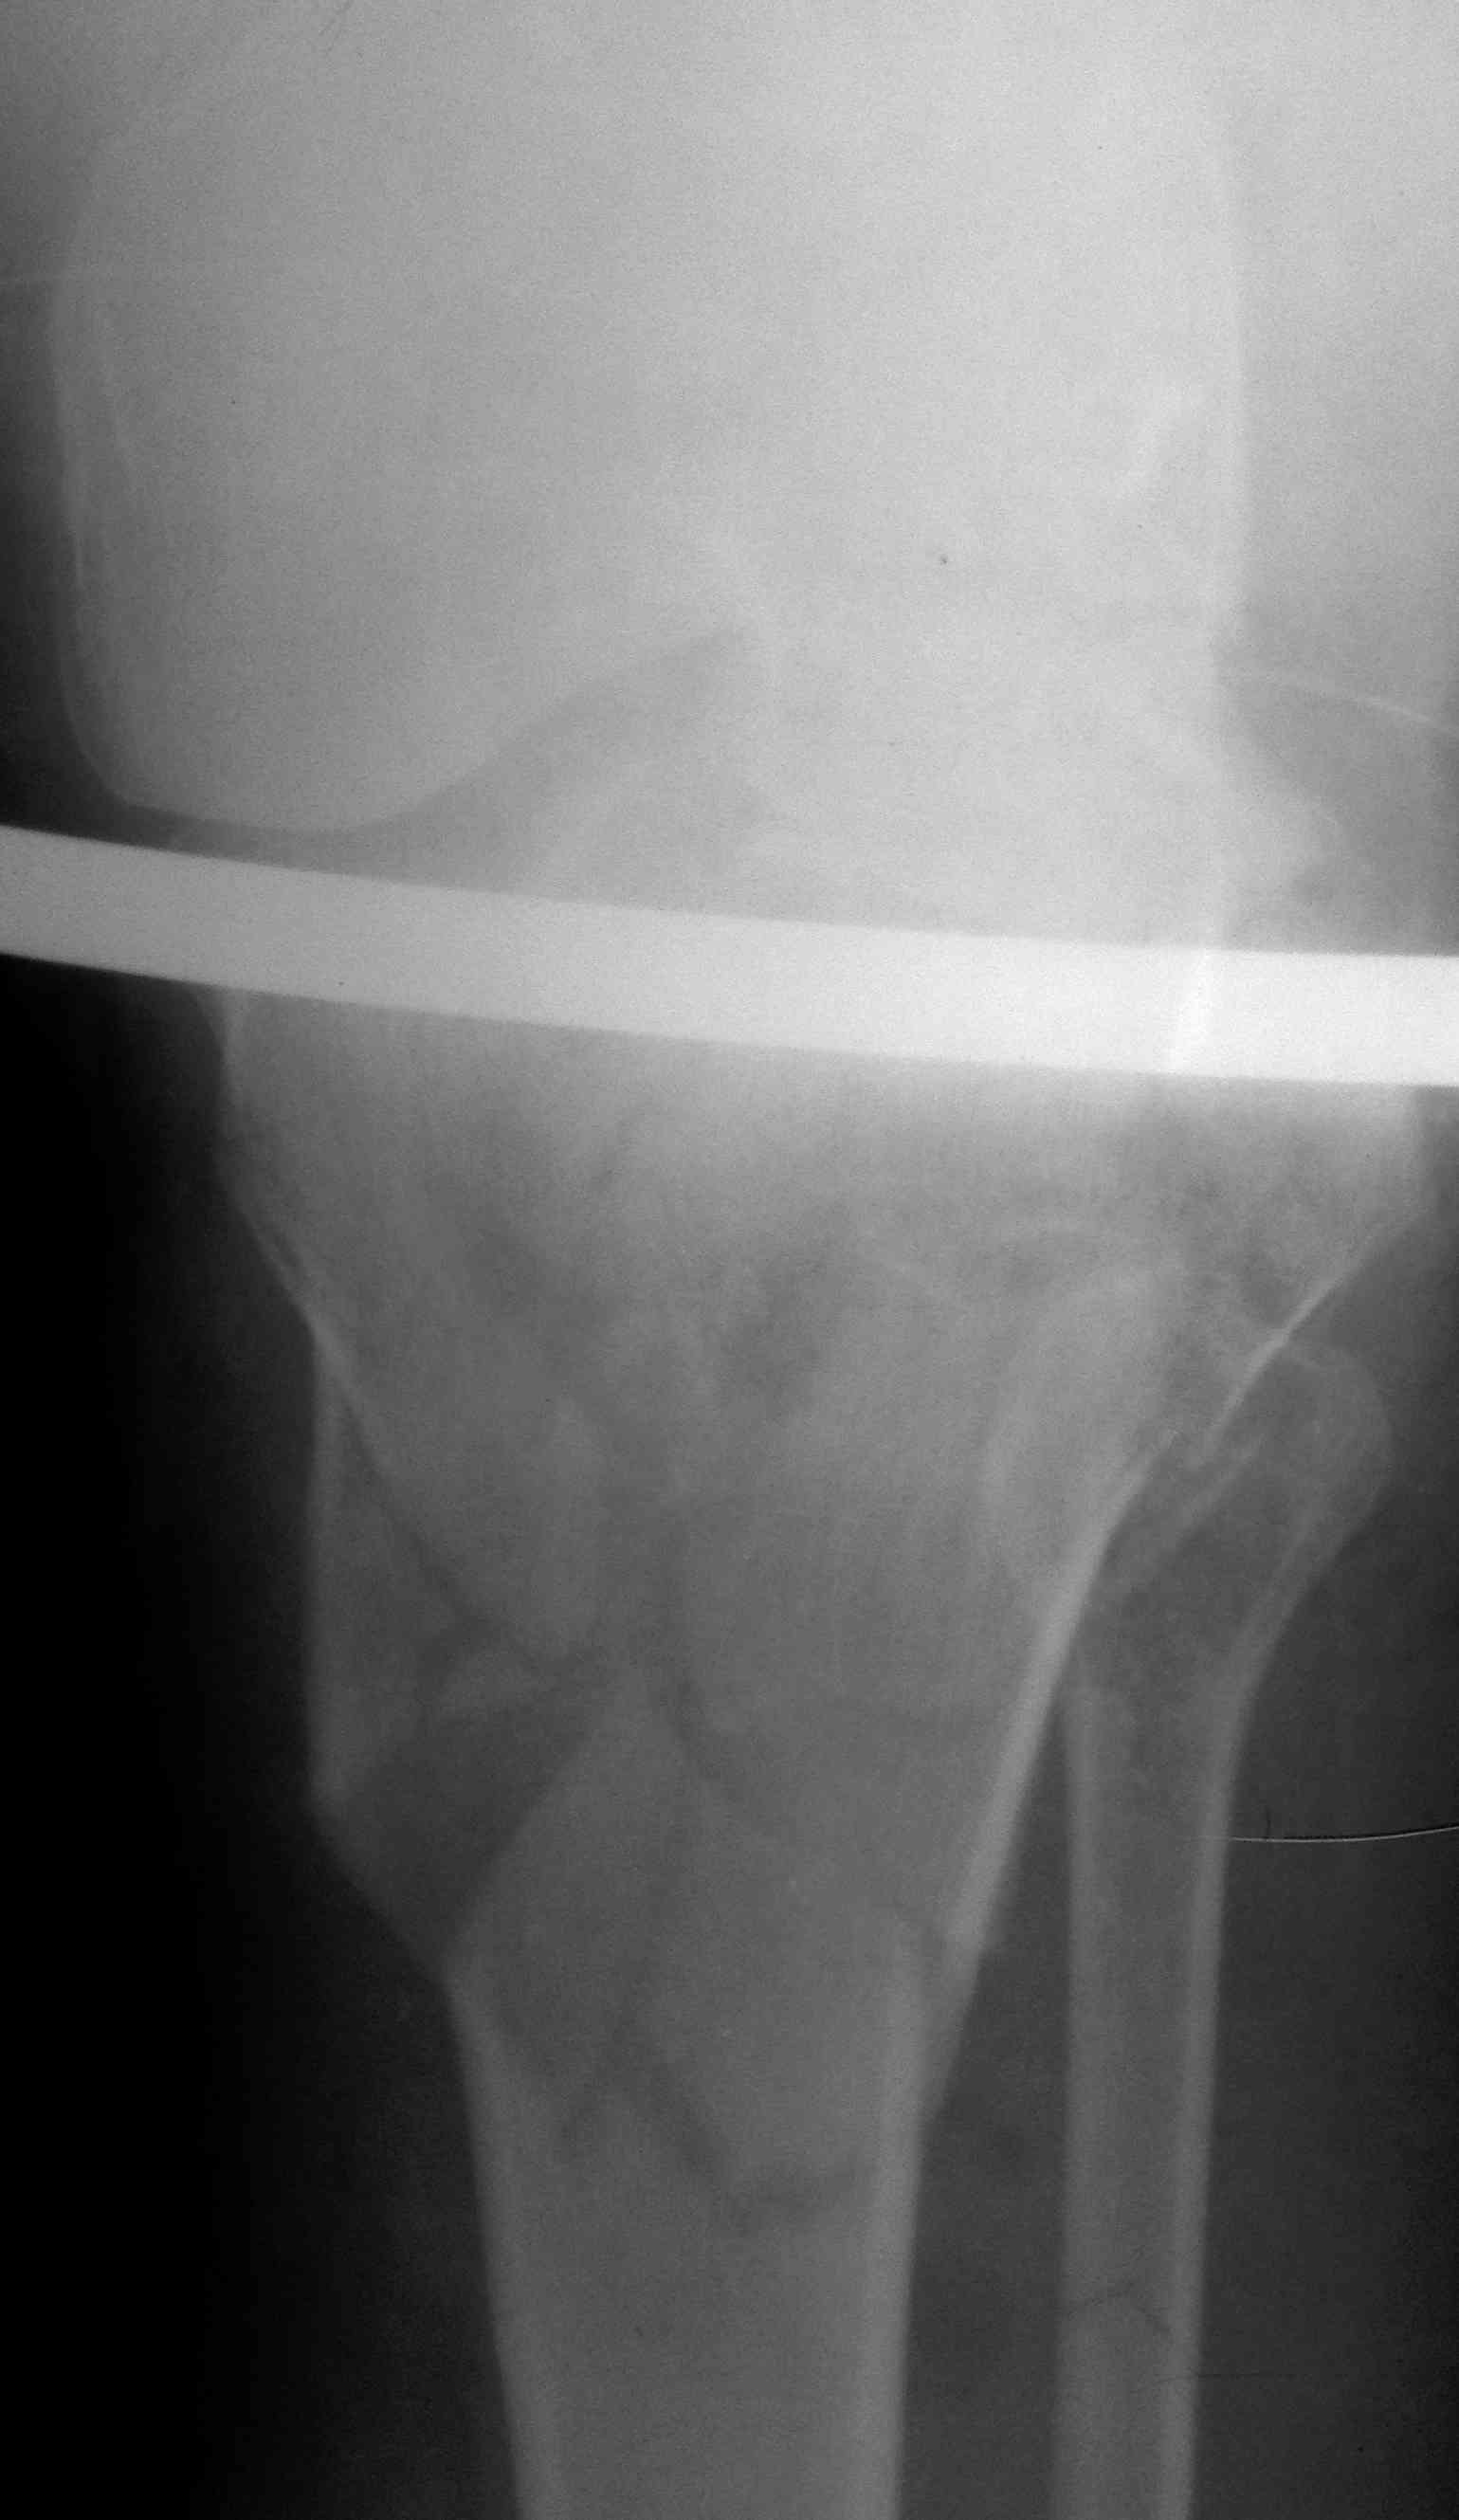

первым этапом сделали синтез задней стенки, дистракционный аппарат на ногу, снимки низкого качества, завтра постараюсь приложить нормальный рентген и КТ

Добрый день, коллеги! Повреждение вертлужной впадины вероятнее всего 62-А1.2 чистый переломовывих, оскольчатый перелом задней стенки, при этом внутрисуставной фрагмент, является частью артикулирующей поверхности ацетабулюм, а следовательно его необходимо извлечь и поместить на место, иначе мозаика может не собраться. Про FAI временно можно не вспоминать (не до него), поскольку наиболее тяжелое повреждение голени требует адекватного вмешательства.На представленных рентгенограммах таза после операции все отлично, полную картину даст КТ.